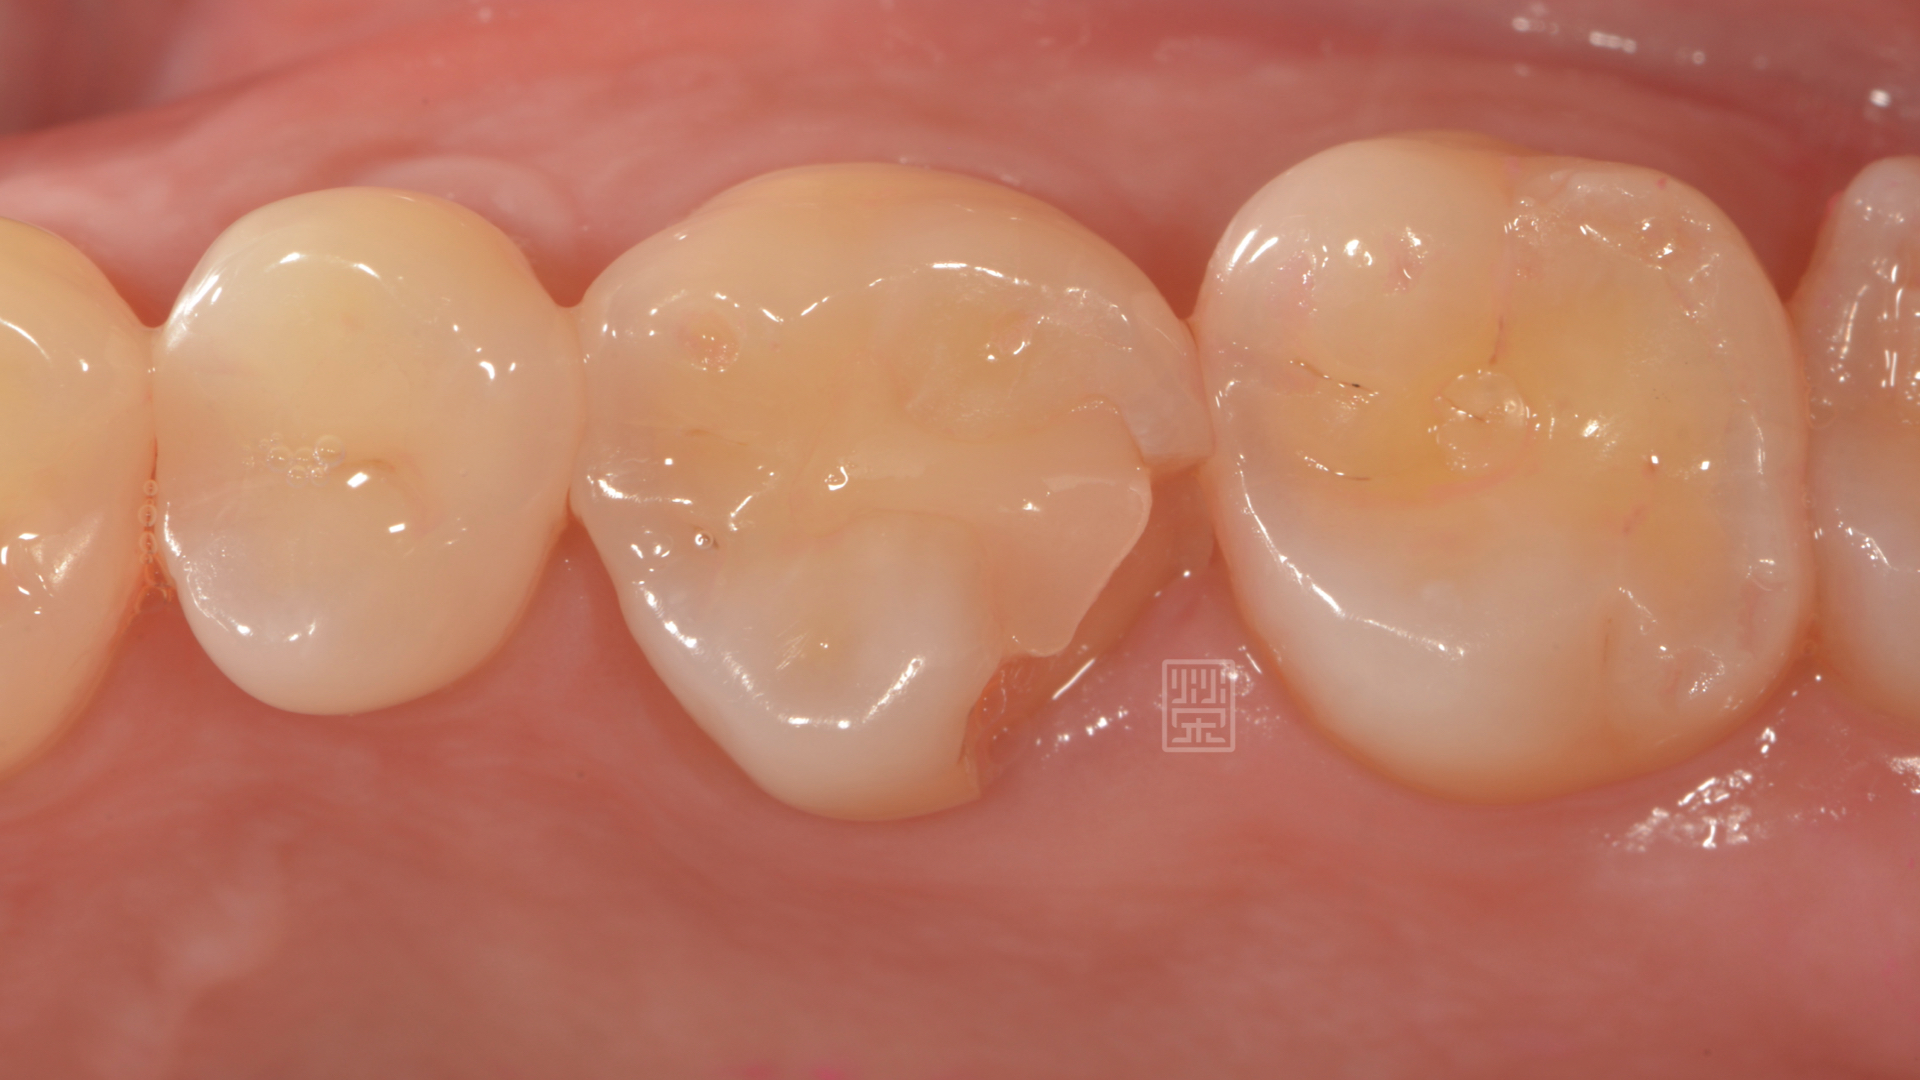

牙齒邊緣破裂